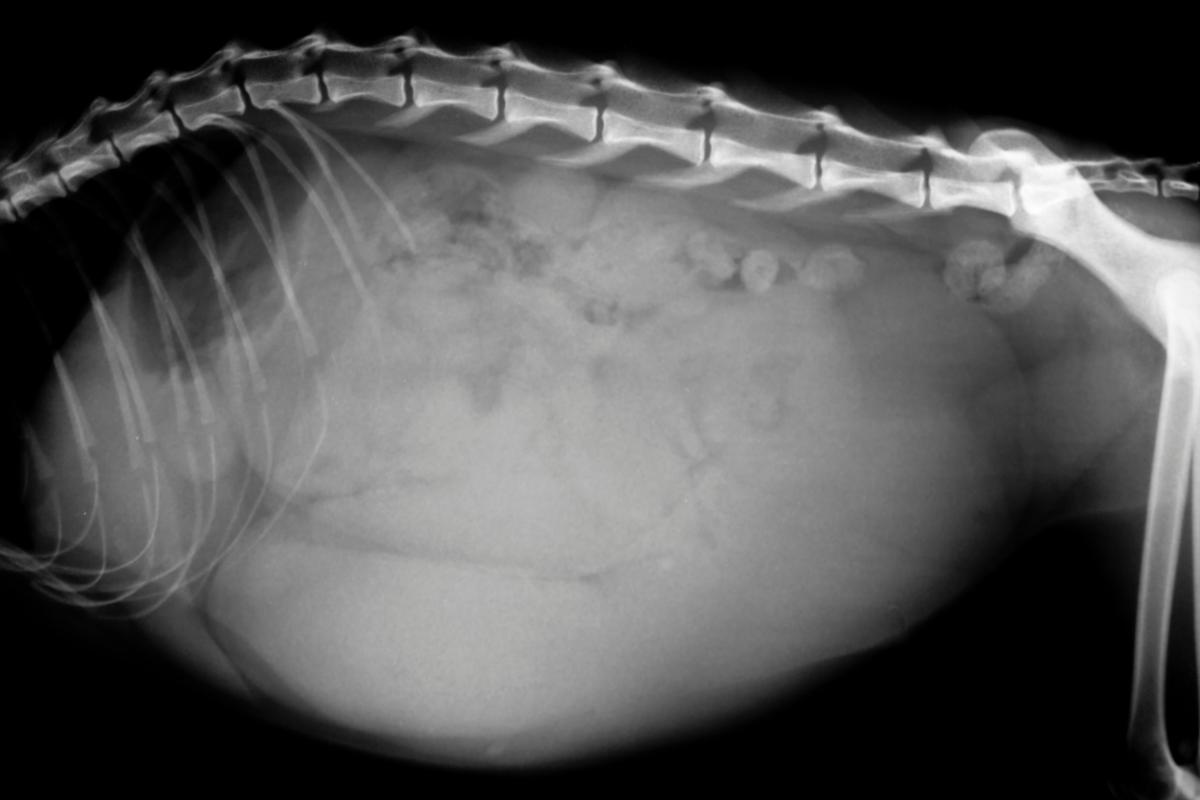

- Distensión abdominal.

- Piometra abierta: el abdomen de la gata se distiende debido a la acumulación de pus dentro del organismo. La gata expulsa a través de la vagina secreciones con mal olor, ya sea de pus o sangre. Es la más frecuente en gatas.

- Piometra cerrada: cuando la gata sufre esta variación de la enfermedad el malestar es todavía mayor, ya que el abdomen se distiende, pero no se expulsa ninguna secreción por la vulva. A consecuencia de esto, la matriz puede llegar a reventar y producir una peritonitis, lo que resulta mortal.

Para que el diagnóstico sea completo, será necesario realizar análisis de sangre y suero sanguíneo, análisis de orina, citología vaginal y la prueba más destacada, la ecografía. Únicamente de esta forma se podrá determinar el tipo de piometra, la gravedad del estado de la matriz y el útero y la extensión de la infección, determinando si se ha complicado con daño al hígado, los riñones u otros órganos.